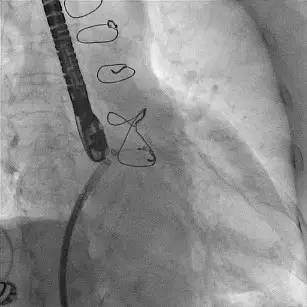

行左心耳封堵术,术前左房肺静脉CTA三维重建如(图1),术中左心耳造影并测量如(图2)(图3),封堵器释放后3D经食道超声心动图(TEE)如(图4)。术后当晚复查超声心动图后,开始应用低分子肝素+华法林,INR达标后,改为华法林+阿司匹林100 mg/d,嘱患者INR控制在1.8~2.5之间。出院1周后患者再次出现咯血,当时测INR 2.0,停用华法林。

图2

图3